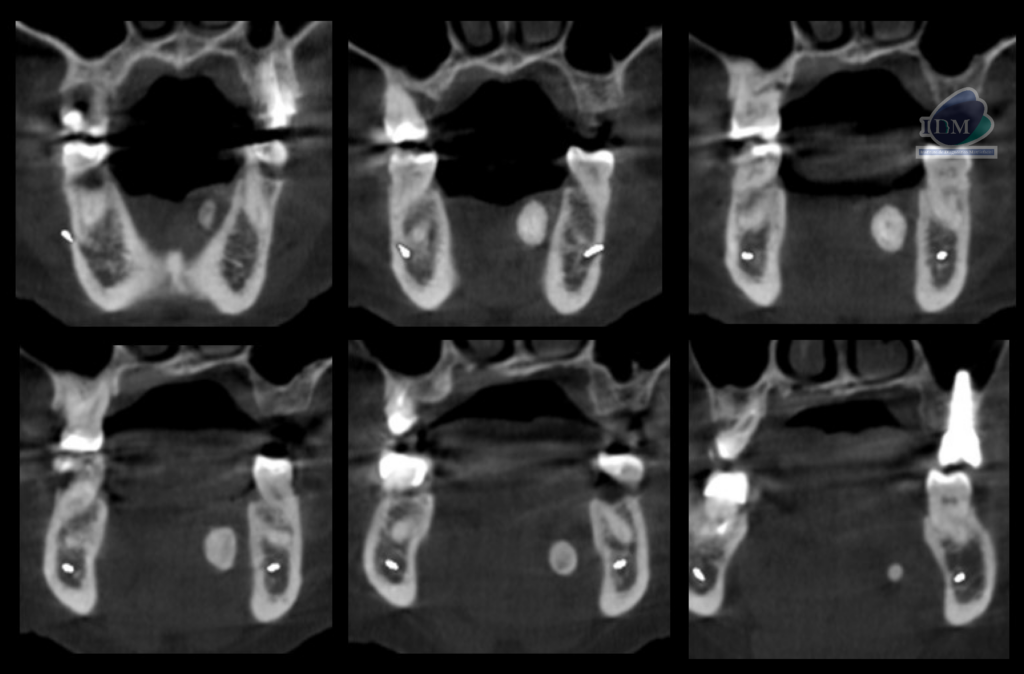

A la evaluación de la tomografía computarizada cone beam en cortes axiales, coronales y transaxiales se observa una imagen hiperdensa con una pequeña área hipodensa central que se localiza por lingual de aproximadamente 20 mm, a nivel del tercio apical de la pieza 33 hasta la raíz distal de la pieza 36. En la reconstrucción en 3D se puede observar de manera más didáctica la relación con las estructuras adyacentes y la forma que presenta, signos imagenológicos compatible con sialolito submandibular.

CORTES CORONALES

CORTES TRANSAXIALES